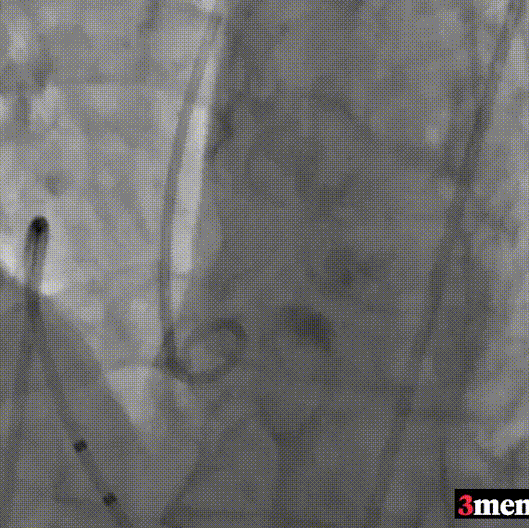

主动脉根部造影